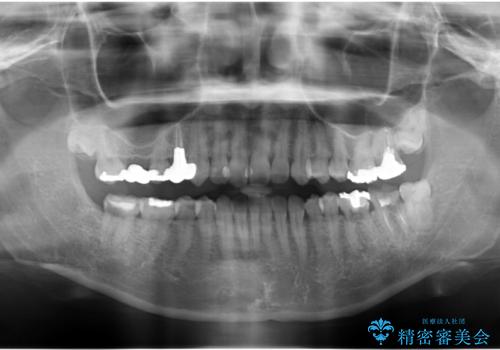

- 奥歯の虫歯を放置してしまい、痛みがあり来院。

過去に他院で親知らず抜歯時に抜けず、長時間恐怖を味わったとのことでトラウマになり歯科にかかることができなかったとのことでした。

下の奥歯が虫歯になっており、痛みが生じていました。

左右の第二大臼歯は虫歯がひどく抜歯が必要な状態でした。

また、左下の第一大臼歯は歯が内側から吸収してしまう状態(外部吸収)が生じており、患者様と相談の上抜歯しました。

合計3本の奥歯を抜歯したところに、インプラント治療を行っています。

また、左上奥歯の根の治療および右下の虫歯治療も併せて行っています。